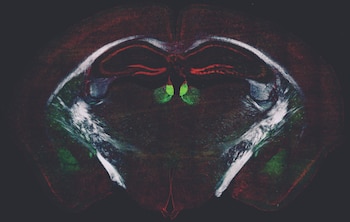

La dopamina se asocia con la motivación y el refuerzo de conductas, mientras que la acetilcolina establece el momento en que las neuronas pueden modificar sus conexiones. La investigación se centró en el cuerpo estriado, una región cerebral que vincula acciones con resultados y evalúa el esfuerzo necesario para lograrlos. Allí, la acetilcolina es liberada por interneuronas colinérgicas, que interrumpen brevemente su actividad durante el aprendizaje, abriendo un “ventana” para que la dopamina fortalezca las conexiones útiles.

Cuando la actividad de Smoothened es alta, las pausas de la acetilcolina son más cortas y reguladas, mientras que, si se elimina este receptor, las pausas se alargan, ampliando el tiempo durante el cual la dopamina puede impulsar cambios. En otras palabras, el equilibrio entre aprendizaje y flexibilidad depende del ajuste fino entre estas dos sustancias.